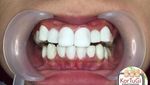

Foto atas adalah contoh veneer yang dilakukan sembarangan vs dilakukan oleh dokter gigi. (Foto: Instagram/korbantukanggigi)